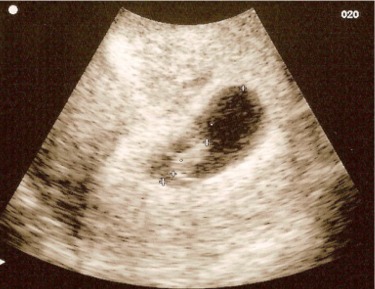

Kép Babuci 8 hetes :)

petezsák: 25,9 mm

babuci: 9,6 mm